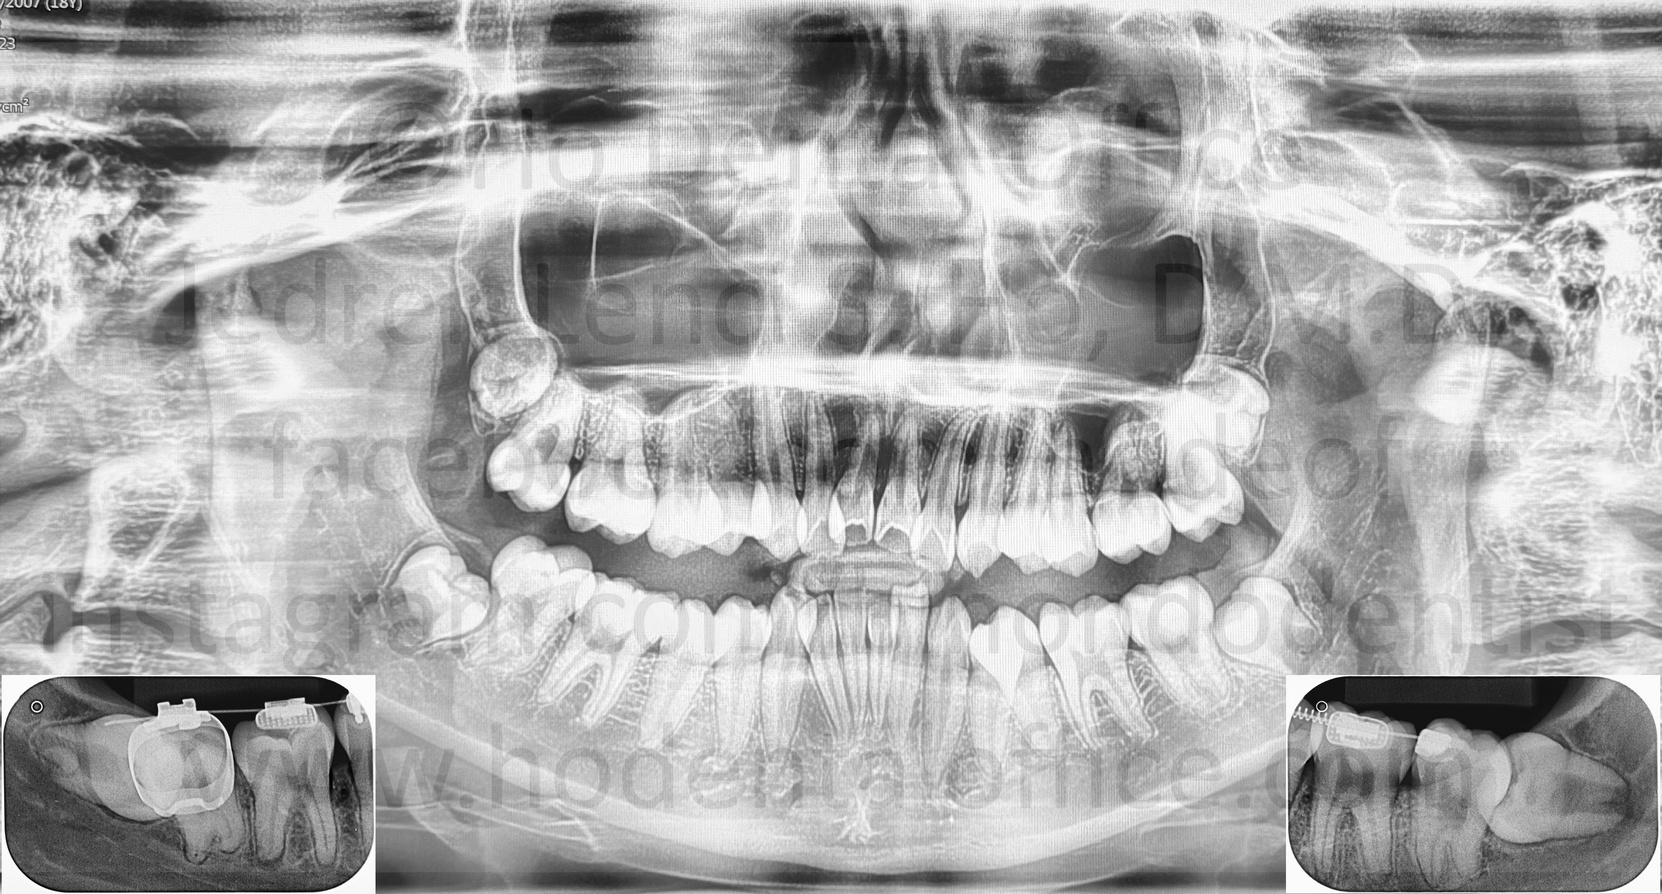

![]() | ![]() | ![]() |

| bone loss due to presence of third molars, note the bone level of the second molar on the side facing the third molar is already on the level of the second molar's roots | ||